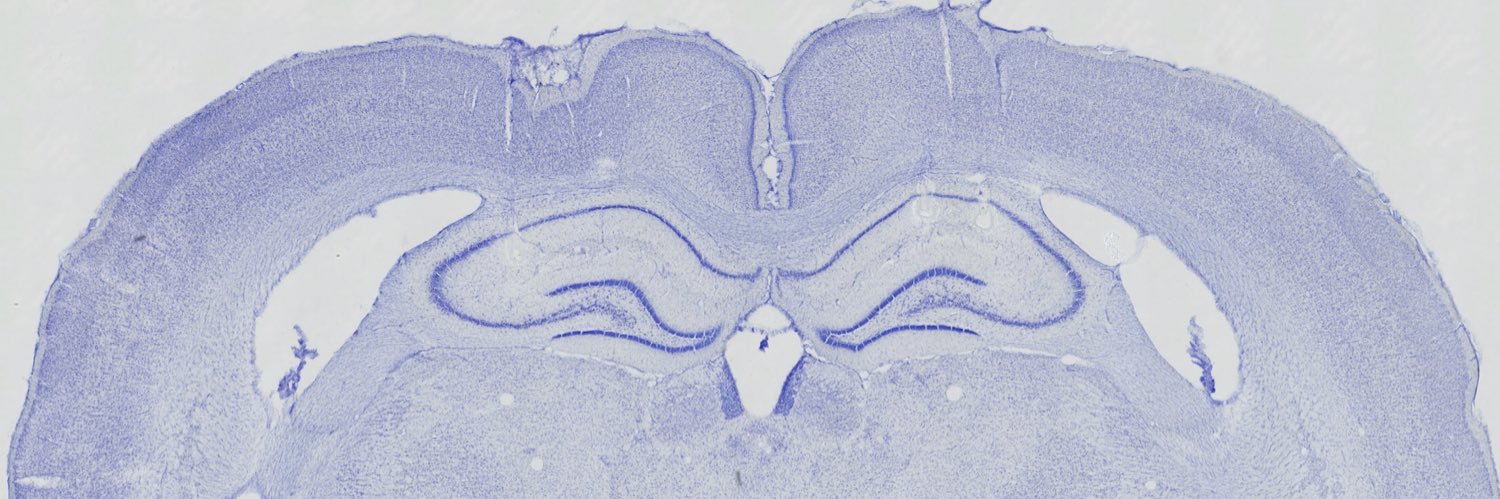

Neuroscience PhD, Brandeis University, Jadhav lab